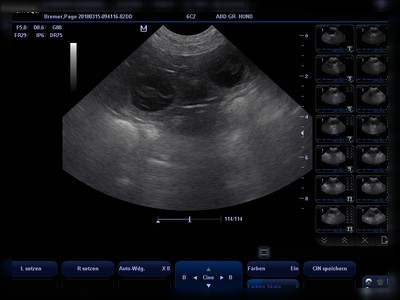

15.03.2018 – 25.Trächtigkeitstag…

Beim heutigen Ultraschall konnten wir mehrere Fruchtanlagen sehen.

Ausgerechnet ist unser G Wurf für den 21/22. April 2018. Page geht es prima, der Appetit ist größer geworden, ohje und wir sind erst am Anfang ;o). Jetzt heisst es für mich hart bleiben… Sehr verschmust ist unsere werdende Mutter geworden, es wird auch mehr geschlafen, man könnte auch sagen es wird gebrütet. Unsere Page startet mit einem Gewicht von 33 Kilo.